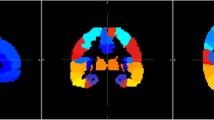

The Dice coefficients of the deep learning methods based on MPRAGE, Dixon, and mUTE images were 0.84 (0.91), 0.84 (0.92), and 0.87 (0.94) for the whole-brain (above-eye) bone regions, respectively, higher than the atlas method of 0.52 (0.64). The regional SUVR error for the atlas method was around 6%, higher than the regional SUV error. The regional SUV and SUVR errors for all deep learning methods were below 2%, with mUTE-based deep learning method performing the best. As for the surface analysis, the atlas method showed the largest error (> 10%) near vertices inside superior frontal, lateral occipital, superior parietal, and inferior temporal cortices. The mUTE-based deep learning method resulted in the least number of regions with error higher than 1%, with the largest error (> 5%) showing up near the inferior temporal and medial orbitofrontal cortices.